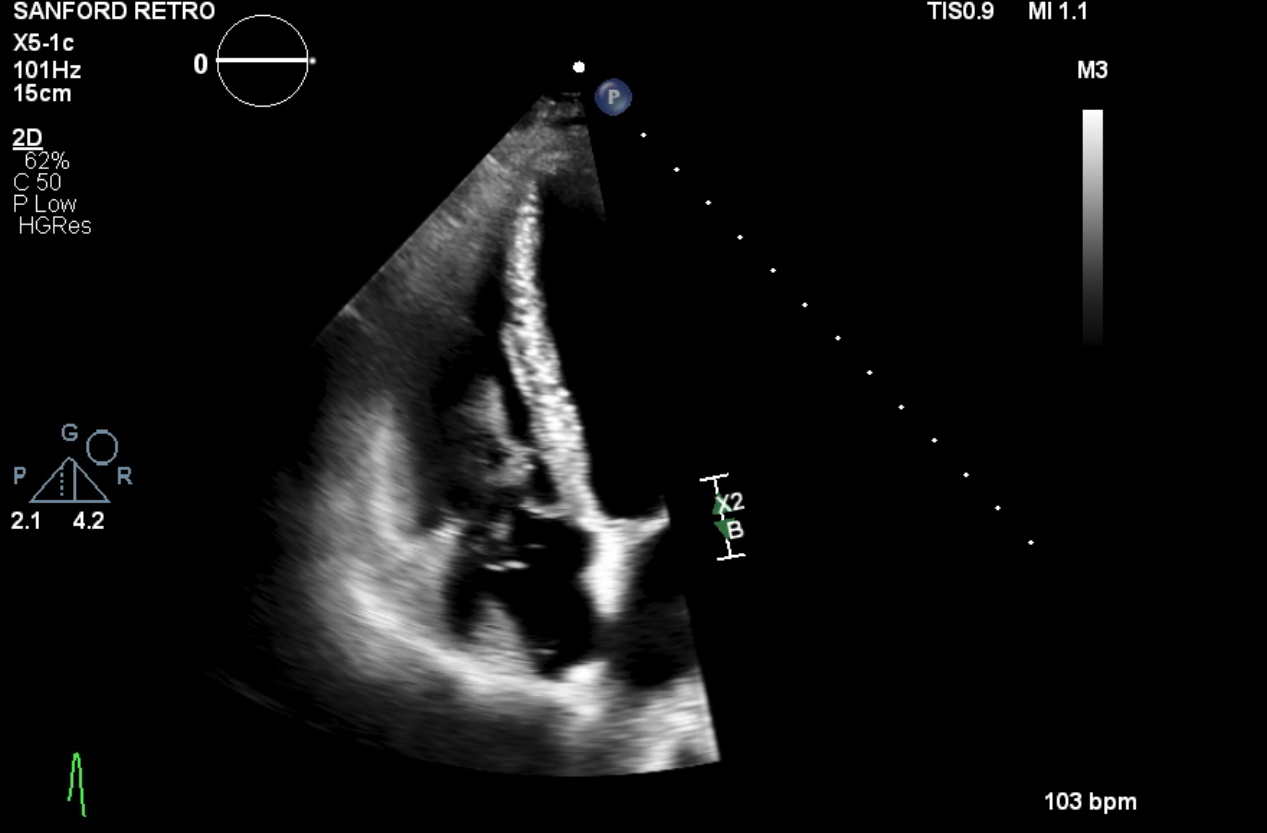

A 48-year-old female with a recent total abdominal hysterectomy for high-grade uterine stromal sarcoma presented for outpatient CT imaging to evaluate disease extent. Imaging revealed extensive IVC thrombus, a small pulmonary embolism, and a possible right atrial thrombus. The patient, who was on prophylactic-dose low molecular weight heparin (Lovenox) and had taken her morning dose, denied leg swelling or pelvic pain. Notably, she had a prior right lower extremity DVT six months earlier following an ankle fracture, treated with a three-month course of anticoagulation. She was referred to the emergency department, where transthoracic echocardiography (TTE) showed a large, mobile thrombus extending into the right atrium and ventricle. She underwent emergent mechanical thrombectomy, with complete removal of the thrombus. Post-procedure transesophageal echocardiography (TEE) confirmed no residual thrombus.